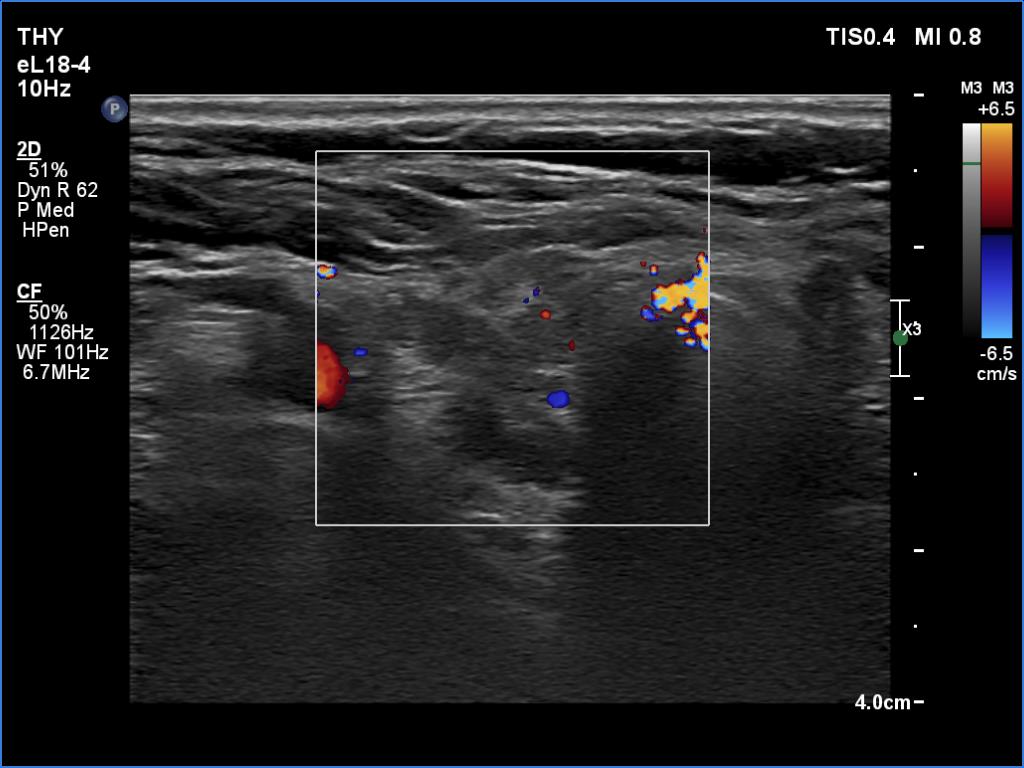

Lymphocytic thyroiditis - case 562 (ultrasonographic picture 3)

Right lobe, transverse scan, color Doppler mode. The lobe is almost avascular.